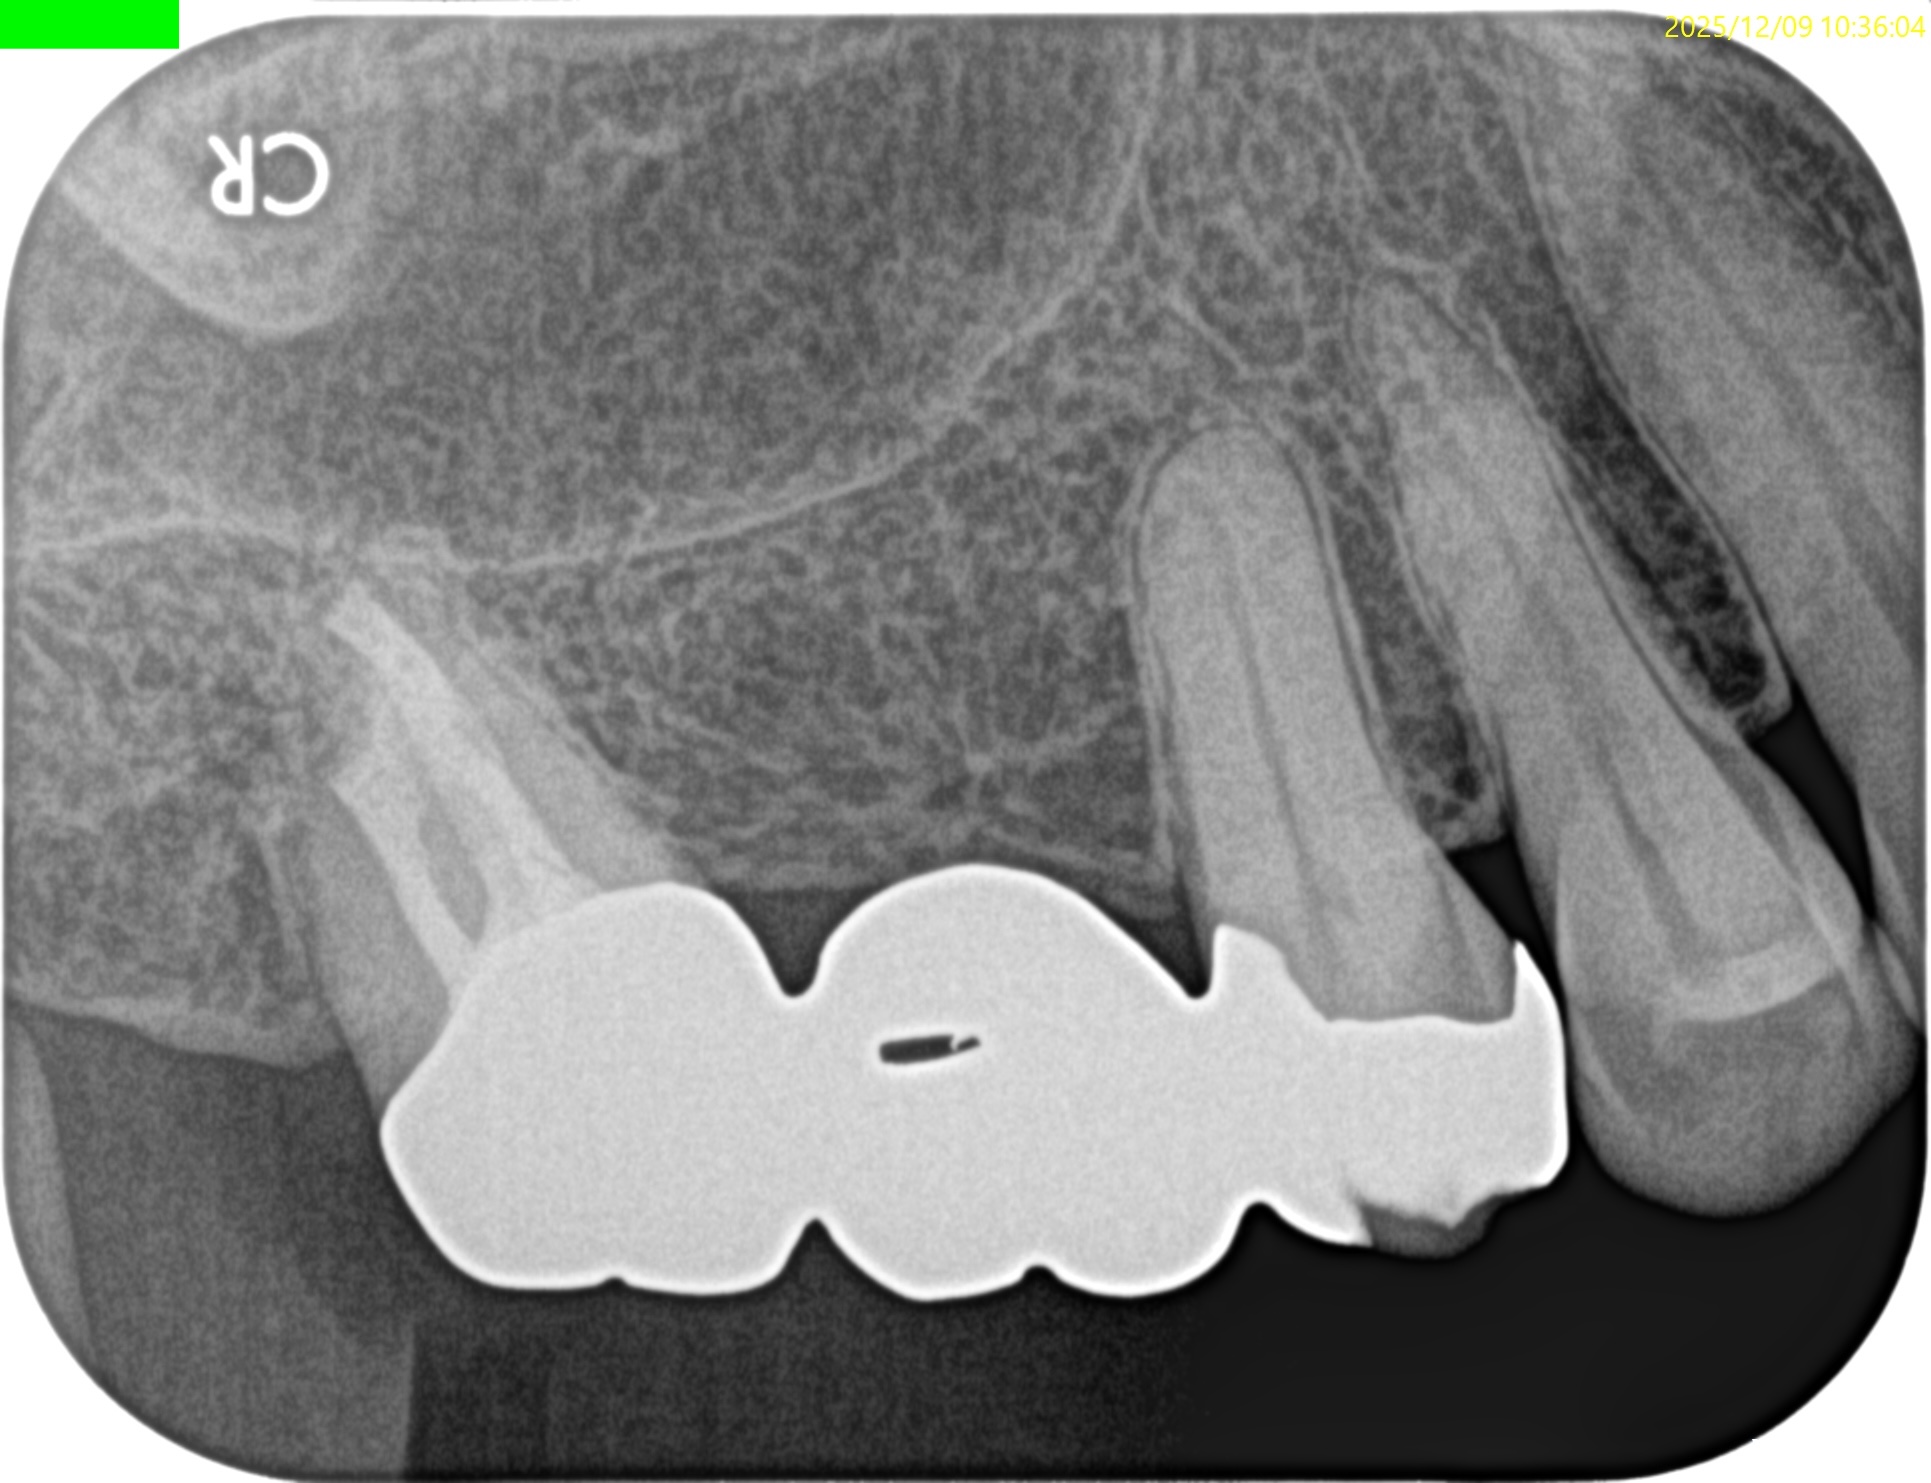

#2 Intentional Replantation 7yr recall(2025.12.9)

問題はない。